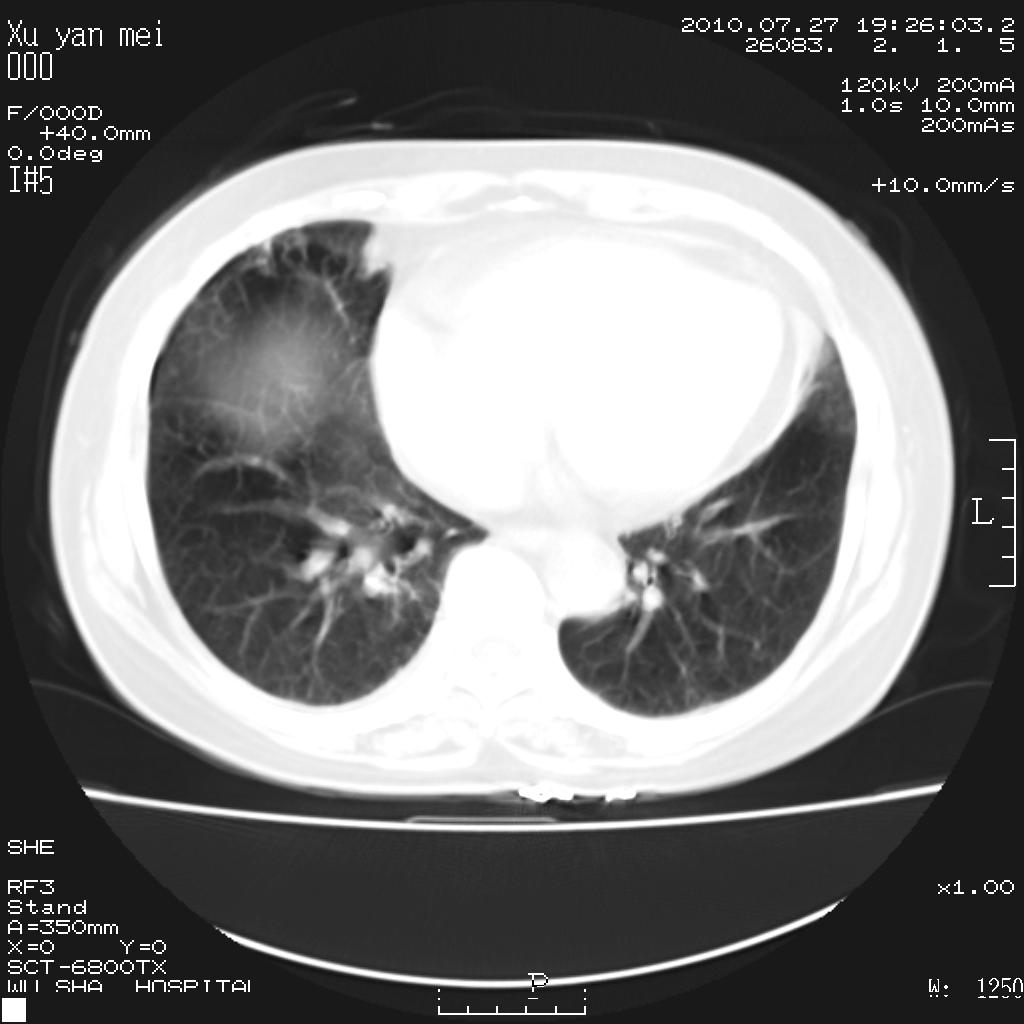

女,60岁,胸痛就诊,右肺结核?炎症?其它?(胸片右侧中上肺野确实看不到什么啊)

1)考虑两肺感染性病变;建议抗炎治疗后复查。2)双侧少量胸腔积液。

1)考虑两肺感染性病变;建议抗炎治疗后复查。2)右侧少量胸腔积液。

双肺炎症可能性大,建议抗炎后复查。右侧胸腔少量积液。双侧胸膜轻度增厚。

考虑两肺感染性病变;不除外肺栓;建议抗炎治疗后复查。